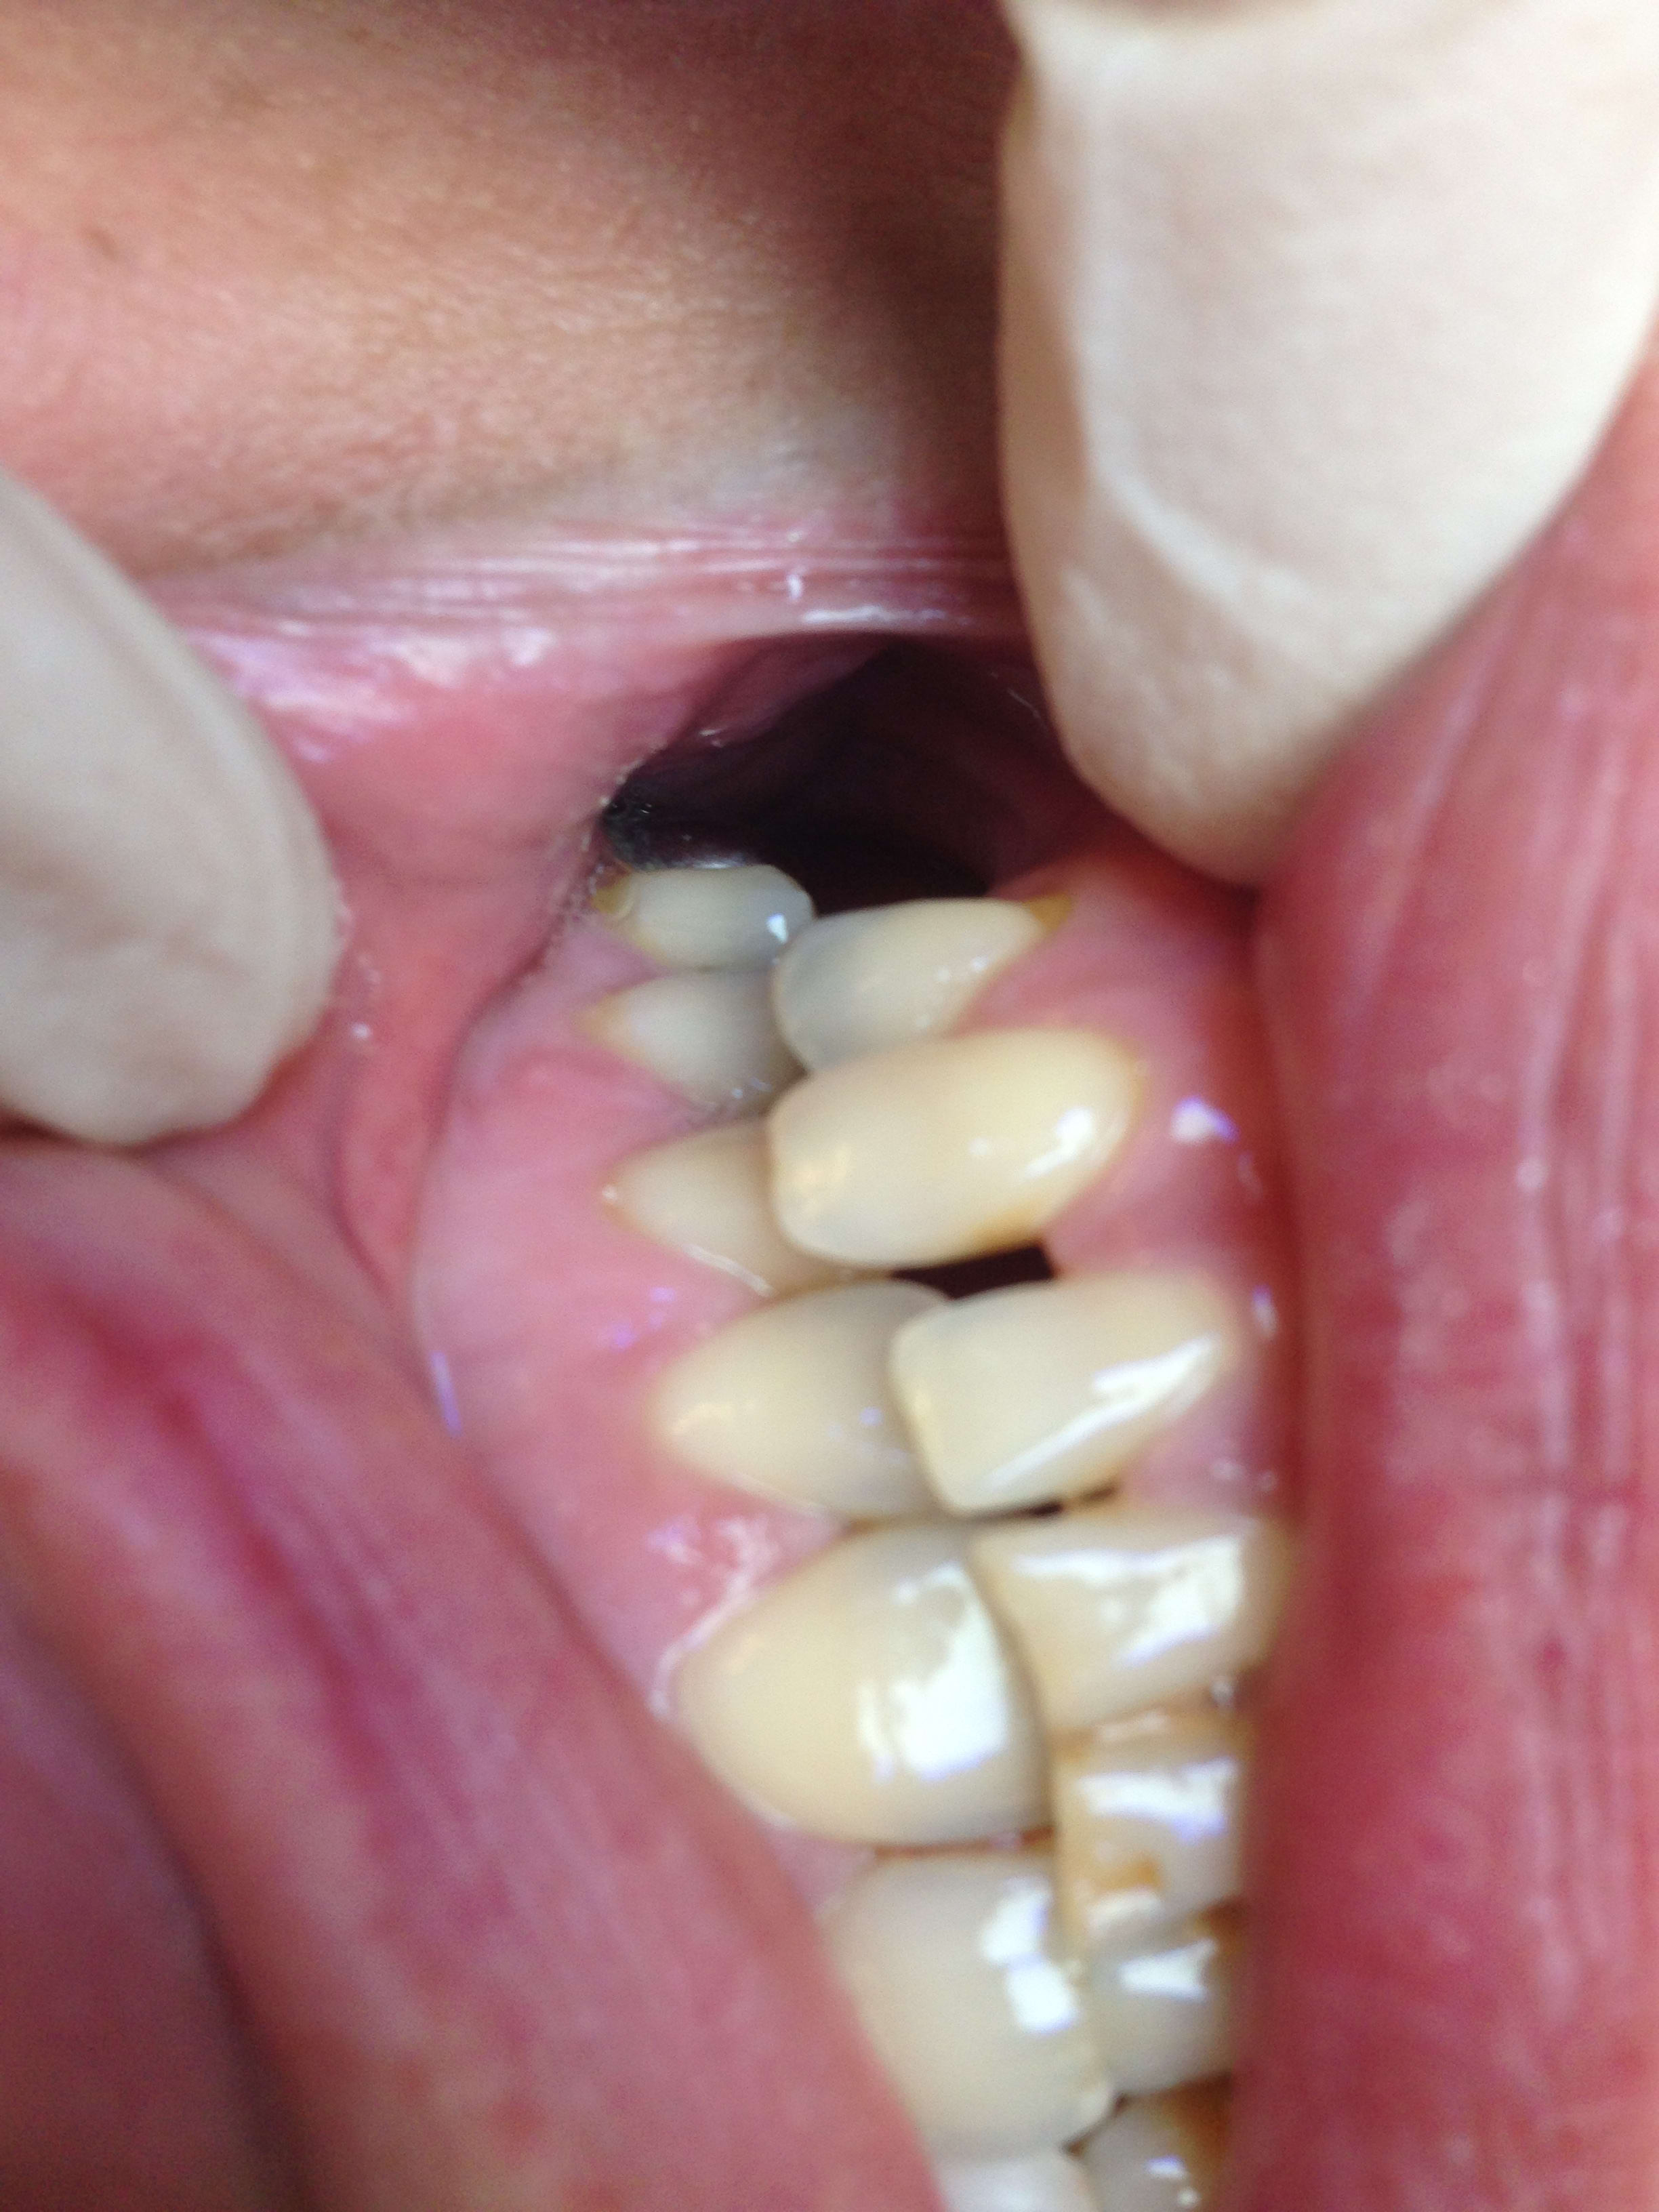

est ce qu'honnêtement c'est possible de récupérer cette vis dans ce cas ? (c'est sur une incisive latérale donc ça doit être du 3mm)

Sur un Implant de 3mm avec la gencive qui pisse le sang juste à coté franchement on y voit que dalle😊

Rapport dent+pilier/implant de 3mm? + connection interne...

Cet implant est à déposer. Le col est abimé, et 2 spires en dehors de l'os. Sans parler de la vis cassée bien entendu

2 spires exposées ne sont absolument pas une raison de virer un Implant

Une vis cassée n'est pas une raison non plus d'enlever un implant

Le col est abîmé je demande à voir .